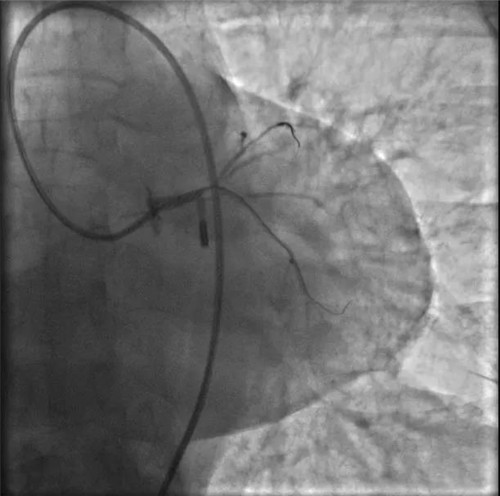

左冠血流保持通暢

確認(rèn)左冠血流保持通暢,大家懸著的心才稍稍放下。

根據(jù)IVUS檢查結(jié)果,在前降支近中段至左主干植入3枚支架,充分?jǐn)U張后,狹窄完全解除,血流恢復(fù)通暢。

植入3枚支架,血流恢復(fù)通暢